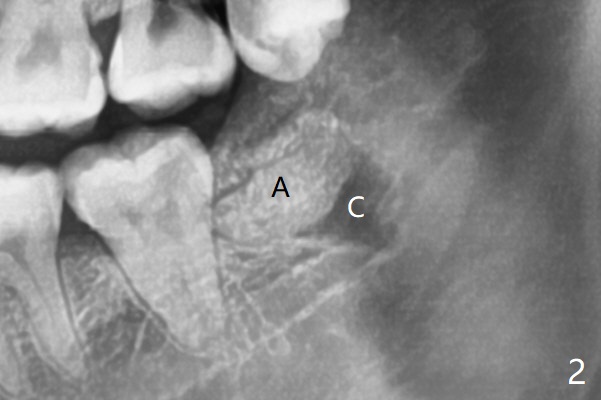

A 24-year-old woman with poor oral hygiene presents to clinic requesting extraction of the tooth #17 (Fig.1). The tooth is removed after multiple sectioning. One half of collagen plug is placed in the bottom of the socket (Fig.2 C, while 1 cc of Bond Apatite in the coronal portion of the socket (A). The other half of the collagen plug is placed on the top of the cement before suturing with 4/0 PGA. The patient feels pain when the tooth is wiggled heavily. But the Inferior Alveolar Canal is not exposed when the tooth is out.